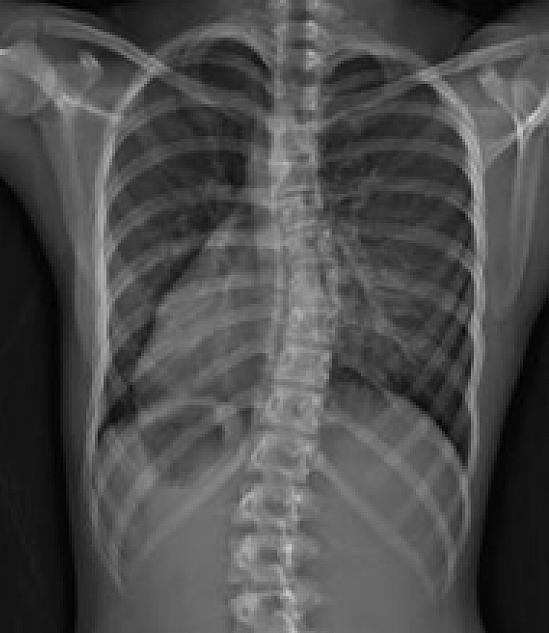

Изза травмы у меня сколиоз, кифоз, остеопороз, тахикардия😭 Травмотолог порекомендовал пройти МСЭ и определить группу инвалидности🥲 пошла один раз на концерт, а получила инвалидность💔😭